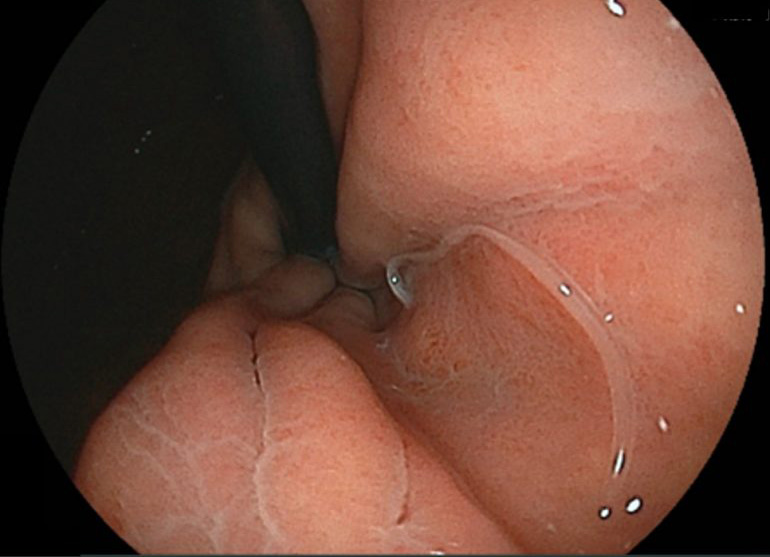

胃アニサキス症

魚介類の寄生虫であるアニサキスを摂取して起こります。主に刺身や加熱が十分ではない魚やイカなどを食べることで感染します。激しい胃の痛みや吐き気・嘔吐といった症状を起こしますが、アニサキスは人間を宿主にできないため1週間程度で死滅して症状はなくなります。ただしかなり痛みが強いため、胃カメラによってアニサキスを除去することをおすすめしています。除去することで痛みなどの症状は消えていきます。

魚介類の寄生虫であるアニサキスを摂取して起こります。主に刺身や加熱が十分ではない魚やイカなどを食べることで感染します。激しい胃の痛みや吐き気・嘔吐といった症状を起こしますが、アニサキスは人間を宿主にできないため1週間程度で死滅して症状はなくなります。ただしかなり痛みが強いため、胃カメラによってアニサキスを除去することをおすすめしています。除去することで痛みなどの症状は消えていきます。